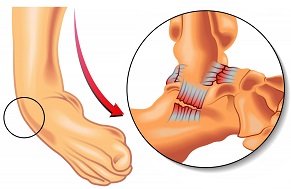

Inflammation in the sinus tarsi canal, a small tunnel between the heel bone and ankle bone

Causes: Ankle sprain, scar tissue, subtalar instability, flat feet

Symptoms: Deep pain, instability, stiffness, pain with ankle movements

Full Article: Sinus Tarsi Syndrome